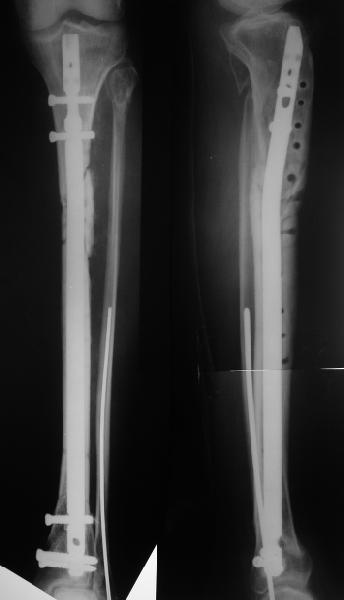

Еще раз спасибо! Сделали вчера. Все прошло по плану, интраоперационное фото после удаления пластинки и итоговые снимки прилагаю. Гвоздь бесканальный 12 мм. Сегодня пациентка уже ходит по палате с одним костылем.

Думаю, через 2-3 месяца - если к этому сроку не будет ярких признаков сращения.